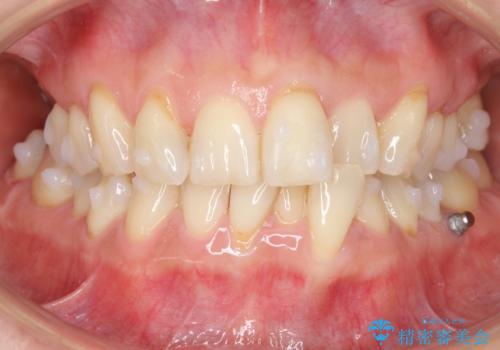

前歯が反対になっている マウスピース矯正+奥歯ブリッジ

- 前歯のがたつきを主訴に来院。

奥歯も少なく、左上奥歯はブリッジにすることになりました。

左下の前歯を中に入れるスペースを確保する目的で左下の奥歯を後ろ移動させました。

また、左下の小臼歯の捻転はマウスピースで治りにくいため、

事前にワイヤーによる部分矯正を行い、矯正用ミニスクリューを植立しています。